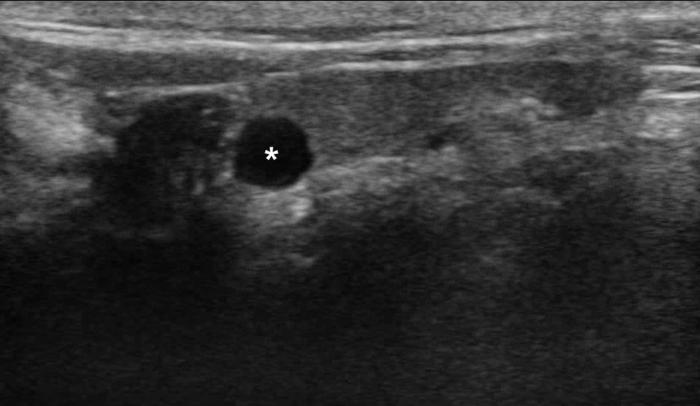

Las glándulas paratiroides, encargadas de la regulación del metabolismo del calcio, pueden ser evaluadas mediante ecografía, aunque su identificación depende de la experiencia del ecografista, la calidad del equipo y la presencia o no de patología subyacente3. En condiciones normales, estas glándulas son pequeñas (menores de 3-4 mm), isoecogénicas o ligeramente hipoecogénicas respecto al tejido tiroideo (Figura 15A-B; ver Figura 2), y se ubican en las proximidades del polo craneal y caudal de cada lóbulo tiroideo1.

En perros y gatos sanos, las paratiroides pueden ser difíciles de visualizar debido a su tamaño y ecogenicidad similar al entorno. Sin embargo, en presencia de hiperparatiroidismo primario o adenomas funcionales, es posible detectar masas redondeadas, bien delimitadas, hipoecogénicas, no dolorosas a la palpación y con diámetro mayor a 4 mm14. El hallazgo de una masa paratiroidea en un paciente con hipercalcemia persistente es altamente sugestivo de enfermedad funcional11.

El uso del Doppler color y espectral ha sido propuesto como complemento diagnóstico, ya que estas lesiones pueden presentar un patrón vascular característico: flujo perilesional con refuerzo interno, aunque no siempre constante19. En casos de hiperplasia bilateral, como en el contexto de hiperparatiroidismo nutricional secundario, pueden observarse múltiples estructuras hipoecogénicas de aspecto similar a ambos lados del cuello, lo que dificulta su diferenciación de otras masas cervicales.

En felinos, la evaluación ecográfica de las paratiroides ha sido documentada en menor medida. No obstante, se han reportado casos en los que se identificaron adenomas paratiroideos funcionales como nódulos solitarios hipoecogénicos de localización paratiroidea, confirmados por estudios histopatológicos o por resolución clínica post-escisión quirúrgica20.